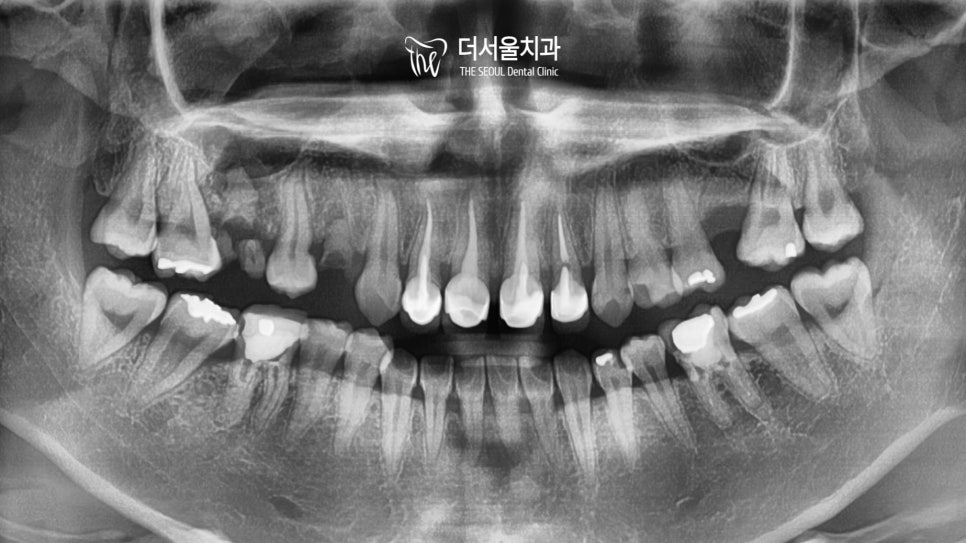

파노라마로 확인했을 때에도

여기저기 남아있는 잔존 치근을 확인할 수 있었으며

측면 세팔로 사진에서는 툭 튀어나오고

뻐드러진 앞니 때문에 입을 다무는 것이

쉽지 않아 보였습니다.